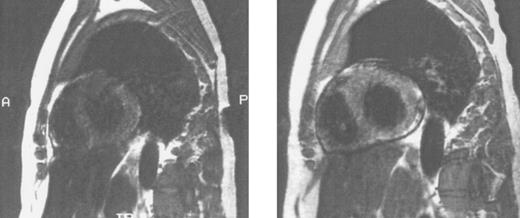

Imaging of tissue iron.Computed tomography,170-174 nuclear resonance scattering (NRS) from manganese-56,175 and the most widely used modality, magnetic resonance imaging,176-193 have all been used to evaluate tissue iron stores in vitro and in vivo, but none is clinically available for the measurement of hepatic iron concentrations. Biopsy-demonstrated reductions in hepatic iron have been reflected by magnetic resonance imaging (MRI) in individual patients192 (Fig 3), but correlations between hepatic iron concentrations determined by biopsy and those estimated by magnetic resonance have varied with differences in both equipment and method. Magnetic resonance represents the only imaging method in clinical use with the potential to detect iron within the heart189,192,193 (Fig 4). Although imprecision in the quantitation of cardiac iron obtained at biopsy194,195 prevents direct correlation with values of cardiac iron estimated by MRI in humans, good correlation between MRI-derived, and biopsy-determined, cardiac iron has been observed in a thalassemic mouse model.193 Furthermore, MRI changes consistent with the reduction of cardiac iron (Fig 5) that are paralleled by improvement in cardiac function have been reported in individual patients.192 Similarly, MRI studies of the iron-loaded anterior pituitary gland196,197 have reported variations in pituitary iron that are correlated with pituitary reserve in individual patients with thalassemia.198 In summary, although many studies show that MRI can reflect the presence of, and changes in, tissue iron in vivo, this method has not been validated as one that provides measurements of tissue iron that are quantitatively equivalent to those determined at tissue biopsy.

Sagittal MRI of the heart in three patients with homozygous β thalassemia and transfusional iron overload. (A, left) Normal signal from the septum (long arrow) and posterior wall of the heart, consistent with the presence of very mild cardiac iron loading, in a transfused patient regularly complianct with iron chelating therapy. The homogenous signal of the liver, consistent with very mild iron loading in this organ (short arrow), is also seen below the image of the heart. (B, middle): Imhomogenity of signal from the septum (long arrow) and posterior wall, consistent with moderate iron deposition in a transfused patient erratically compliant with iron chelating therapy. Loss of liver signal (short arrow) is consistent with heavier iron loading in this organ. (C, right): Absence of signal from the septum (arrow), posterior wall and liver (short arrow), compatible with heavy iron deposition in a transfused patient who has been noncompliant with iron chelating therapy over several years.

Sagittal MRI of cardiac iron before (left) and after (right) therapy with the orally active iron chelating agent deferiprone in the same patient with homozygous β thalassemia whose liver histology and hepatic MRI are shown in Fig 3. Imhomogenity of cardiac signal in the MRI on the left is compatible with significant iron deposition, while improvement in signal intensity after nine months of chelating therapy indicates that the cardiac iron content is reduced compared with that of the previous study. (Reprinted with permission.192 )